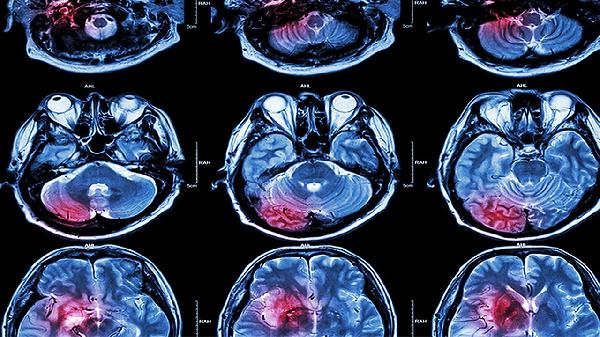

脑溢血患者该吃哪些药?实用用药指南来啦

脑溢血患者在治疗过程中必须严格按照医生的指导用药,常用的药物包括甘露醇注射液、呋塞米片、氨甲环酸注射液、奥拉西坦胶囊以及胞磷胆碱钠片等。由于脑溢血属于一种危急重症,药物的使用需要根据出血量、位置以及是否有并发症综合判断,患者和家属切勿擅自服药。